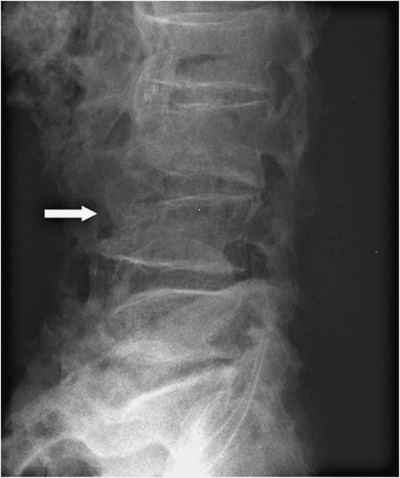

На 3-й день после состоявшегося осмотра участковым врачом выполнена рентгенограмма поясничного отдела позвоночника (см. рис. 1).

Заключение в поликлинике: остеохондроз поясничного отдела позвоночника, остеофиты всех поясничных позвонков. Компрессионные изменения L4.

Рисунок 1. Рентгенограмма поясничного отдела позвоночника

В результате изучения представленной рентгенографии мы констатируем наличие дегенеративно-дистрофических изменений позвоночника в форме остеоартритических изменений (включая деградацию межпозвонкового хряща); возможны протрузии дисков. Следует отметить, что, помимо вышеописанного, обращает на себя внимание остеопороз тел позвонков с компрессионным переломом L4.